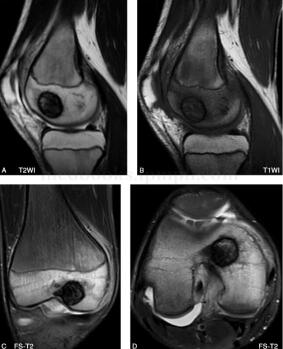

图3 MR:右肱骨远端骨骺内类圆形病灶(25mm×19mm),边界清晰,内部信号不均匀、以低信号为主。邻近髓腔内及软组织内可见水肿信号。关节囊内积液

成软骨细胞瘤(图4)

图4 病理:瘤细胞密集,多角形,弥漫分布,核膜厚、界清,内有多核巨细胞,瘤细胞间有软骨样基质和格子钙化